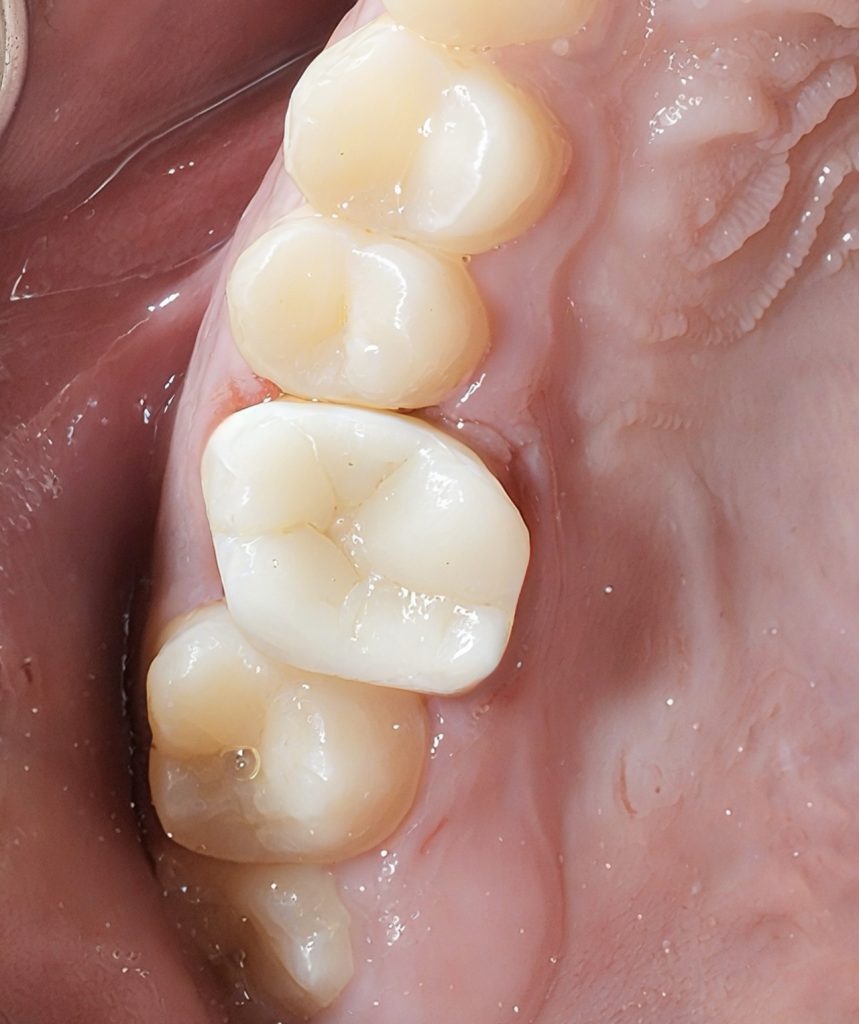

8. FINAL OUTCOME

The result shows:

- Restored biomechanics

- High aesthetics

- Smooth contours that support gingival health

- Stable occlusion with minimal material thickness

The combination of:

Endodontic cleaning + strong adhesive core + DME + composite onlay

gives the tooth a second life with maximum preservation of natural structure.